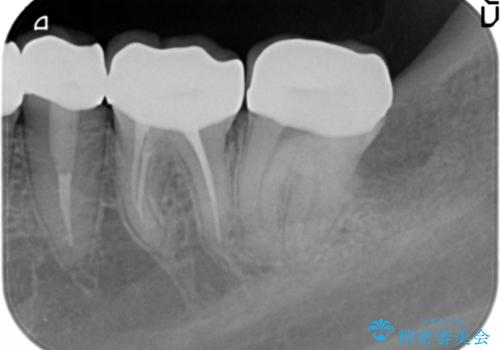

- 憧れの芸能人(ヴィジュアル系バンドマン)のような歯になりたいとのご希望で来院された患者様です。

咬み合わせが悪く矯正も検討されていたそうですが、歯を真っ白にしたいというご希望もあり、28本のすべての歯をセラミックにしたいとのことでした。

精査したところ、ほとんどの歯が保険内のレジンで充填されており、咬み合わせも悪く咬合していない歯もありました。

虫歯をしっかりと治療したのち、オールセラミッククラウンによる補綴治療を行いました。

下顎の埋伏していた親知らずも抜去しました。